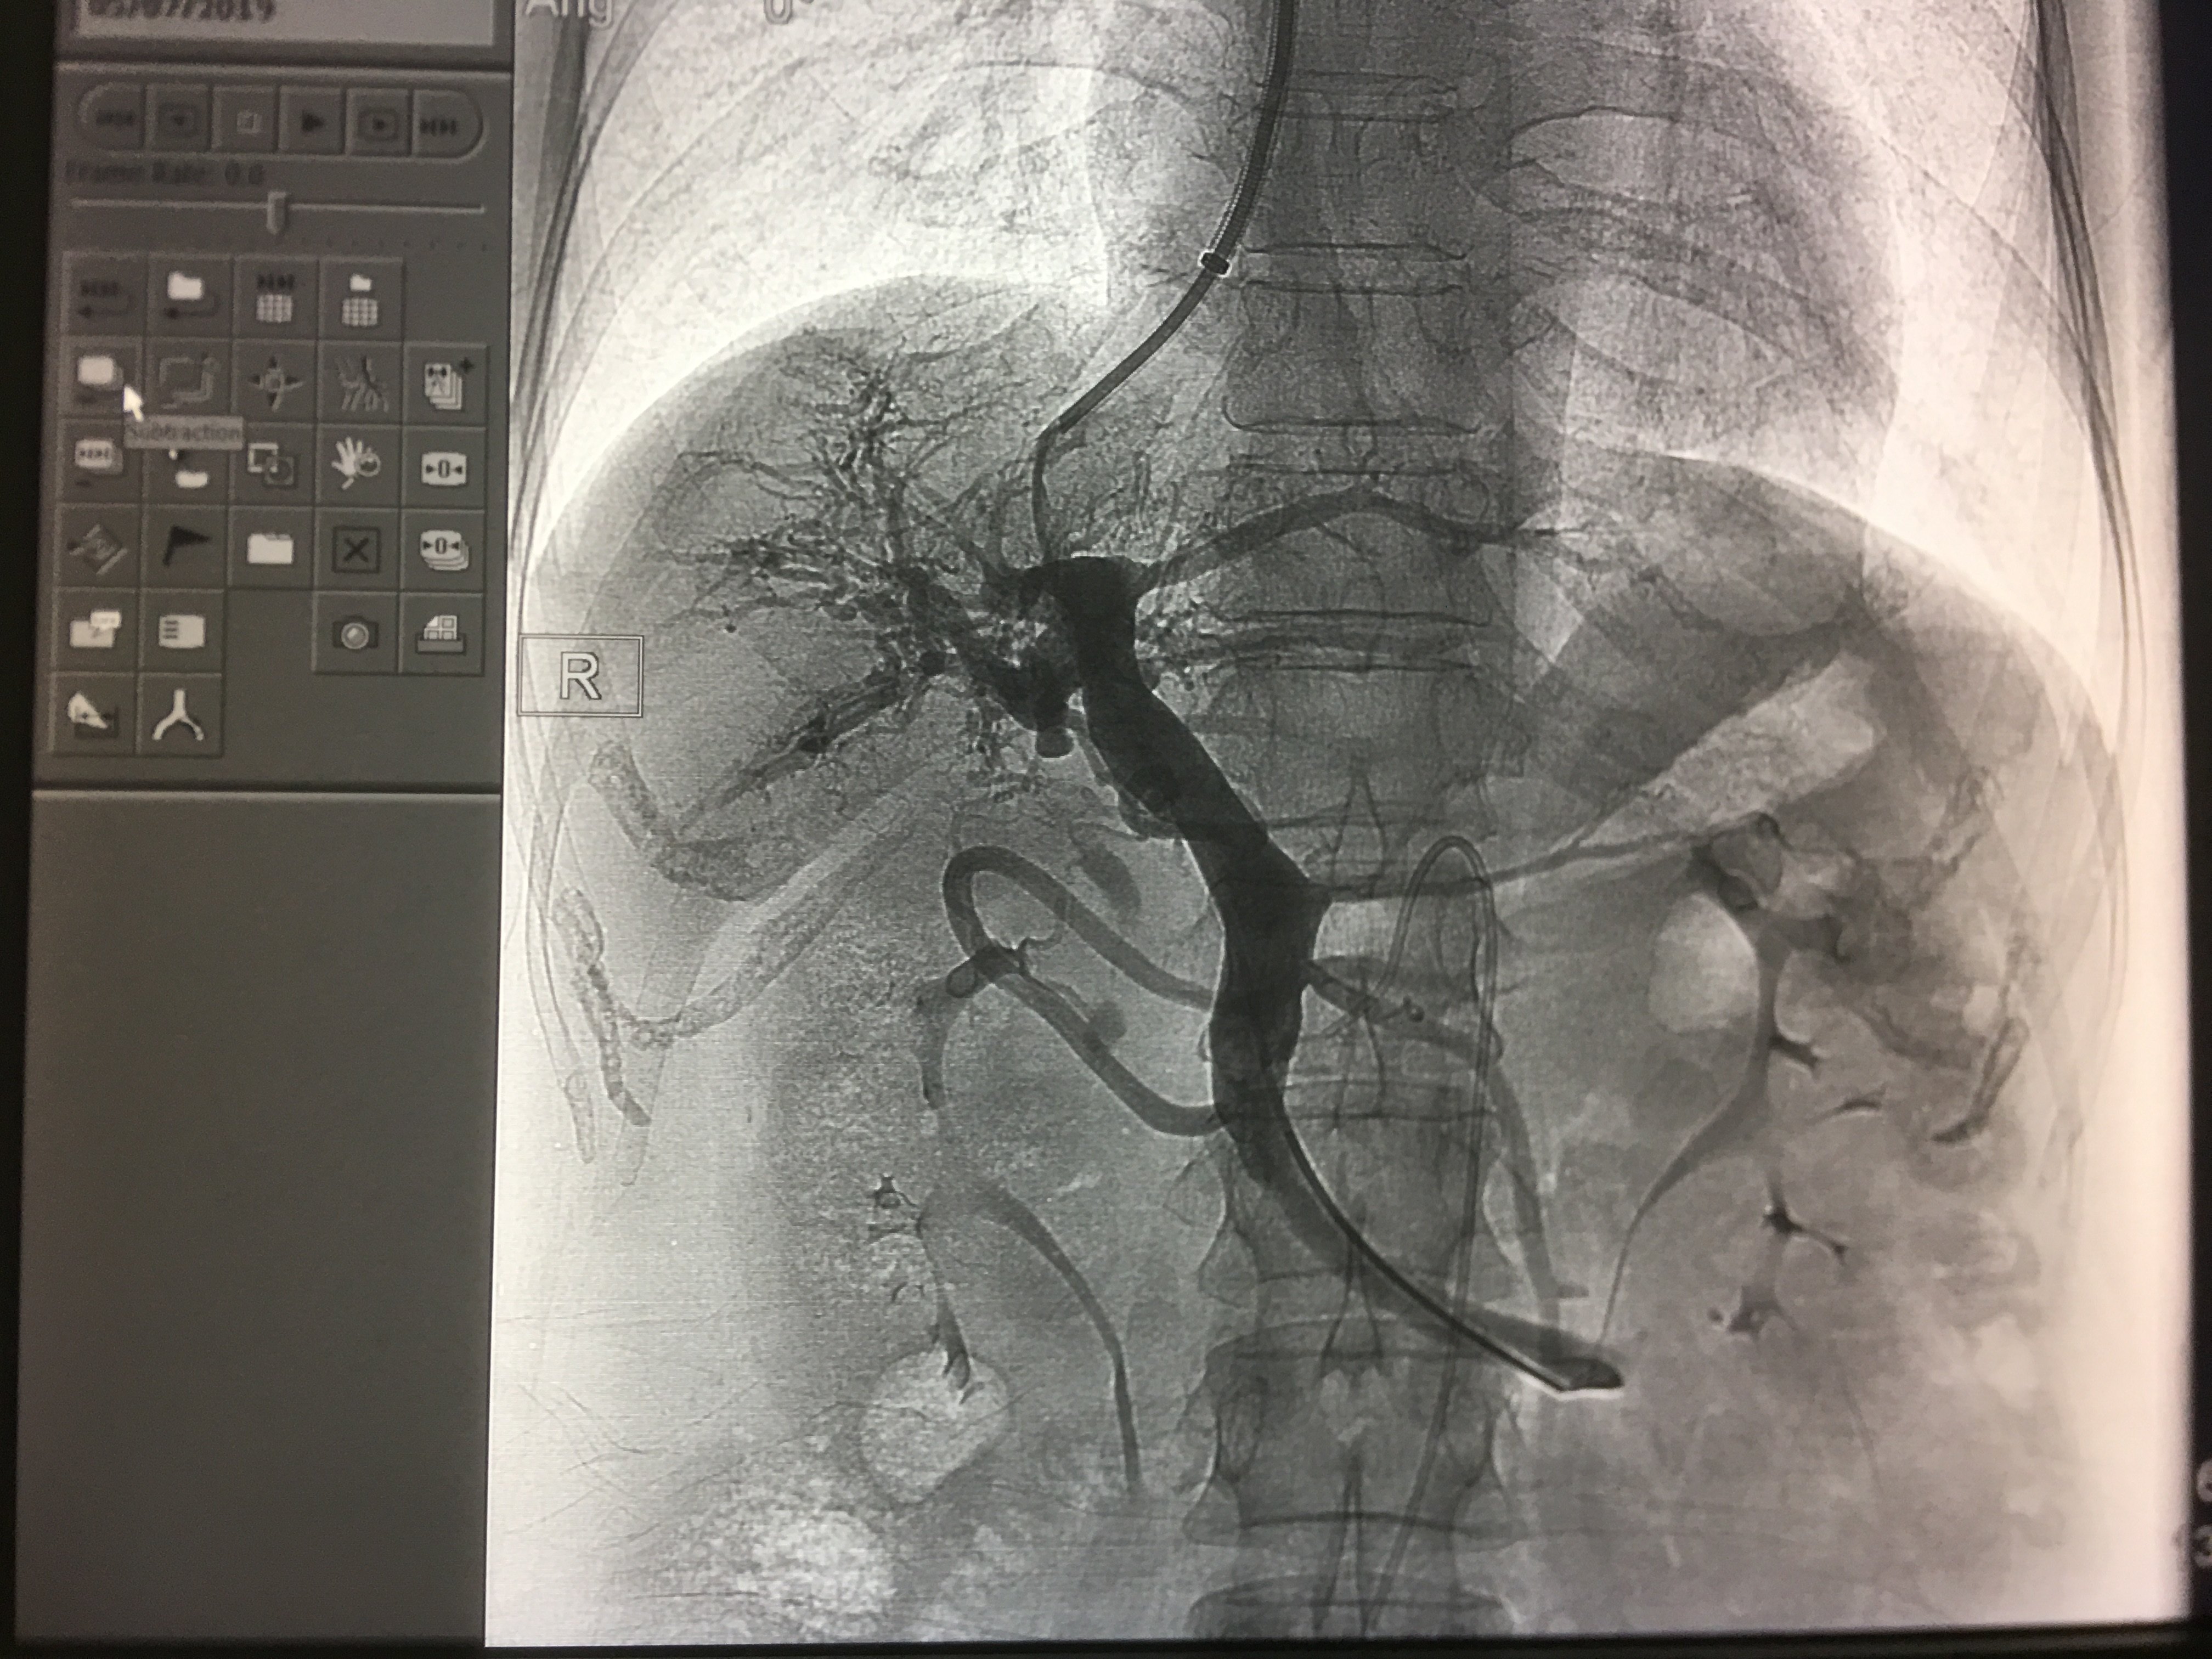

胃底静脉曲张栓塞